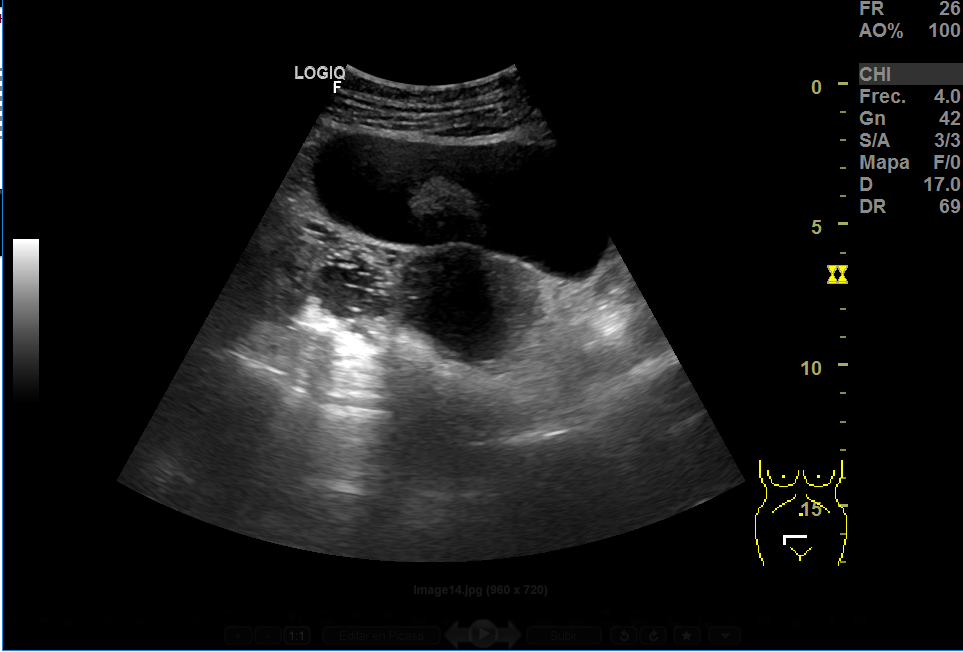

Realizamos una ecografía en el centro de salud y objetivamos, adyacente a útero, una imagen heterogénea de gran tamaño (15x8 cm), con vascularización, que podría corresponder a un mioma gigante. En anejo derecho, imagen redondeada de aproximadamente 3 cm en cuyo interior aparecen líneas hiperecogénicas en un fondo hipoecoico que podrían corresponder a teratoma, sin descartar otra patología. Ante la duda, derivamos a ginecología.

La RMN confirma la masa fibrótica de 11x8x10 en relación con mioma pediculado. Imágenes en la línea medida de fondo saco de Douglas de 55x46 y otra de 37x36, bien delimitadas, hiperintensas, compatibles con teratomas.

La anatomía patológica ha confirmado el dx de mioma y de teratomas bilaterales.